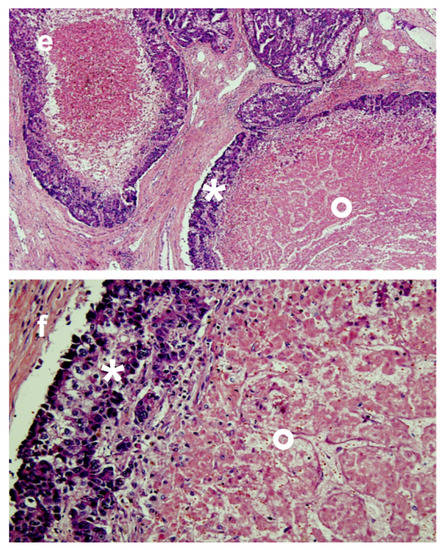

- Crocetti, L.; Scalise, P.; Bozzi, E.; Campani, D.; Rossi, P.; Cervelli, R.; Bargellini, I.; Ghinolfi, D.; De Simone, P.; Cioni, R. Microwave Ablation of Very-Early- and Early-Stage HCC: Efficacy Evaluation by Correlation with Histology after Liver Transplantation. Cancers 2021, 13, 3420. [Google Scholar] [CrossRef] [PubMed]